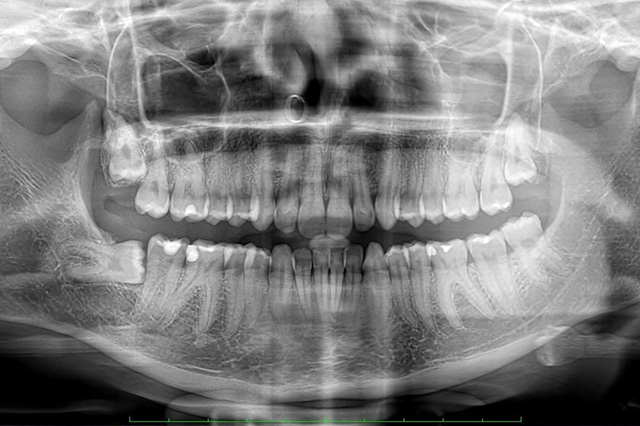

La radiologia odontoiatrica utilizza tecniche di imaging per diagnosticare e pianificare il trattamento delle condizioni dentali e orali. Le immagini radiografiche forniscono informazioni dettagliate sui denti, le ossa mascellari e le strutture circostanti, aiutando i dentisti a valutare problemi che non sono visibili ad occhio nudo.

Le principali tecniche di radiologia odontoiatrica includono TC Dentascan, RVG-radiovisiografia, scanner intraorale ai fosfori, ortopantomografia digitale a basso dosaggio (OPT), teleradiografia digitale di ultima generazione

La radiologia odontoiatrica è essenziale per una diagnosi accurata e una pianificazione efficace del trattamento, garantendo così risultati migliori e una gestione più sicura delle patologie dentali.